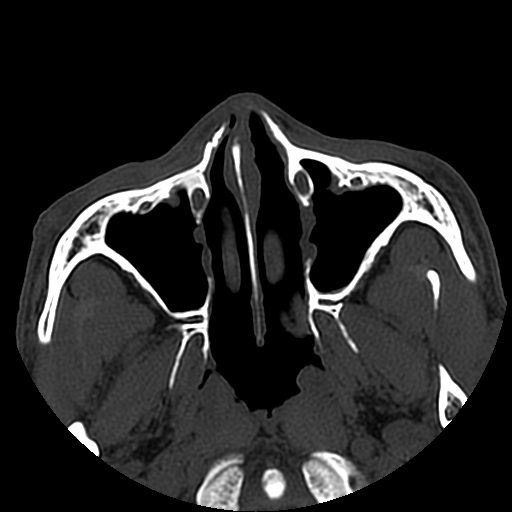

以下是引用liaoqiang在2008-7-16 21:15:00的发言:[br]右侧鼻骨骨折

以下是引用zxd95在2008-7-16 21:39:00的发言:[br]右侧上颌骨额突骨折。[br][br][br][br]